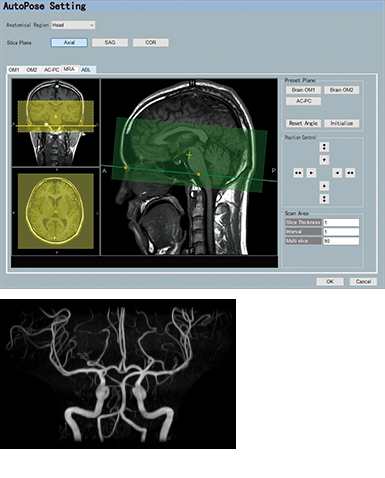

AutoPose is a slice line setting support function.

When the Scanogram imaging ends, the preset section is automatically set and can be registered up to five types of preset sections.

When AutoExam is executed, clipping is performed automatically after MRA imaging.

MRA

with AutoClip